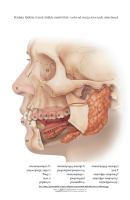

Näo ja suu anatoomia

1